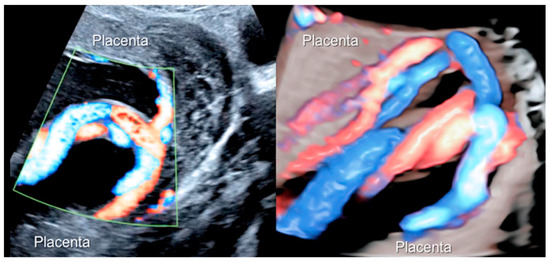

3.2.1. Nuchal Cords